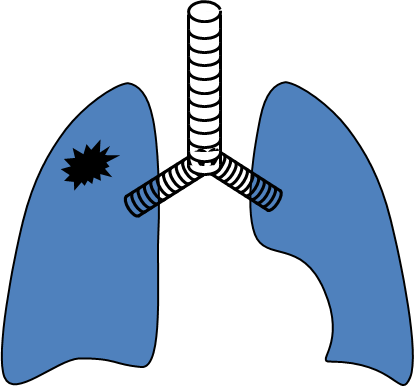

Şəkil 10. Ağciyər absesinin yaranma mexanizmləri və gedişi

Klinik təsnifatda ağciyər xərçəngi 3 mərhələyə bölünür:

- Erkən mərhələ - mediastinal yayılma yoxdur (I-II mərhələlər)

- Yerli yayılmış mərhələ - mediastinuma yayılma var (IIIA və B mərhələlər)

- Metastaz mərhələsi - distal metastazlar var (IV mərhələ) (Şəkil 10).